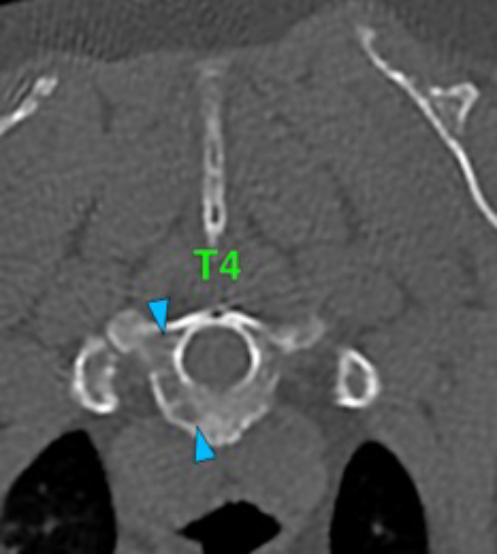

There are multiple osteolytic lesions affecting almost all the vertebral bodies (red arrows). Some of them are areas of permeative or moth-eaten lysis, while others converge into geographic lesions. They affect all the different portions of the vertebra (vertebral body, spinous and transverse processes, etc.) and involve the medullary cavity of the bone (blue arrows), and some of them cause lysis of the cortex (green arrows). Lumbar vertebral bodies more severely affected.

The osteolytic lesions have soft tissue attenuation that shows moderate and slightly heterogeneous post-contrast enhancement. In some of the vertebrae, the lesions cause lysis of the cortex and extend into the vertebral canal (orange arrows) causing variable degree of compression of the spinal cord and cauda equina (blue arrows). At the level of the vertebral bodies of T7, T8, T9 and T12 the lesions extend into the ventral and central aspect of the vertebral canal causing a mild compression of the spinal cord. At the level of T13, L1, L4 and L5 the lesions extend into the ventral and central aspect of the vertebral canal, causing moderate compression of the spinal cord. At the vertebral body of L6 the lesion extends into the ventral and central aspect of the vertebral canal, at the mid-aspect of L6, occupying approx. 90% of the diameter of the vertebral canal causing a severe compression of the cauda equina. At the level of L7, the lesion extends into the ventral and both lateral aspects of the vertebral canal, causing severe compression of the cauda equina.